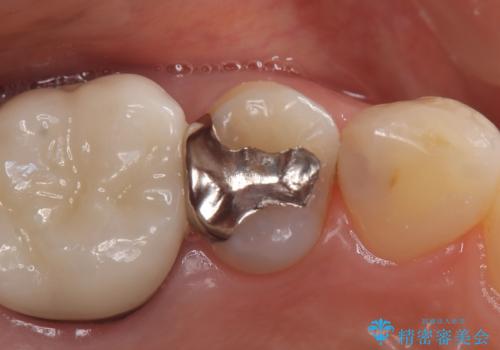

- 定期検診にてむし歯が見つかった患者さまです。

金属アレルギー体質とのことで、セラミックインレーにて修復治療を希望されました。